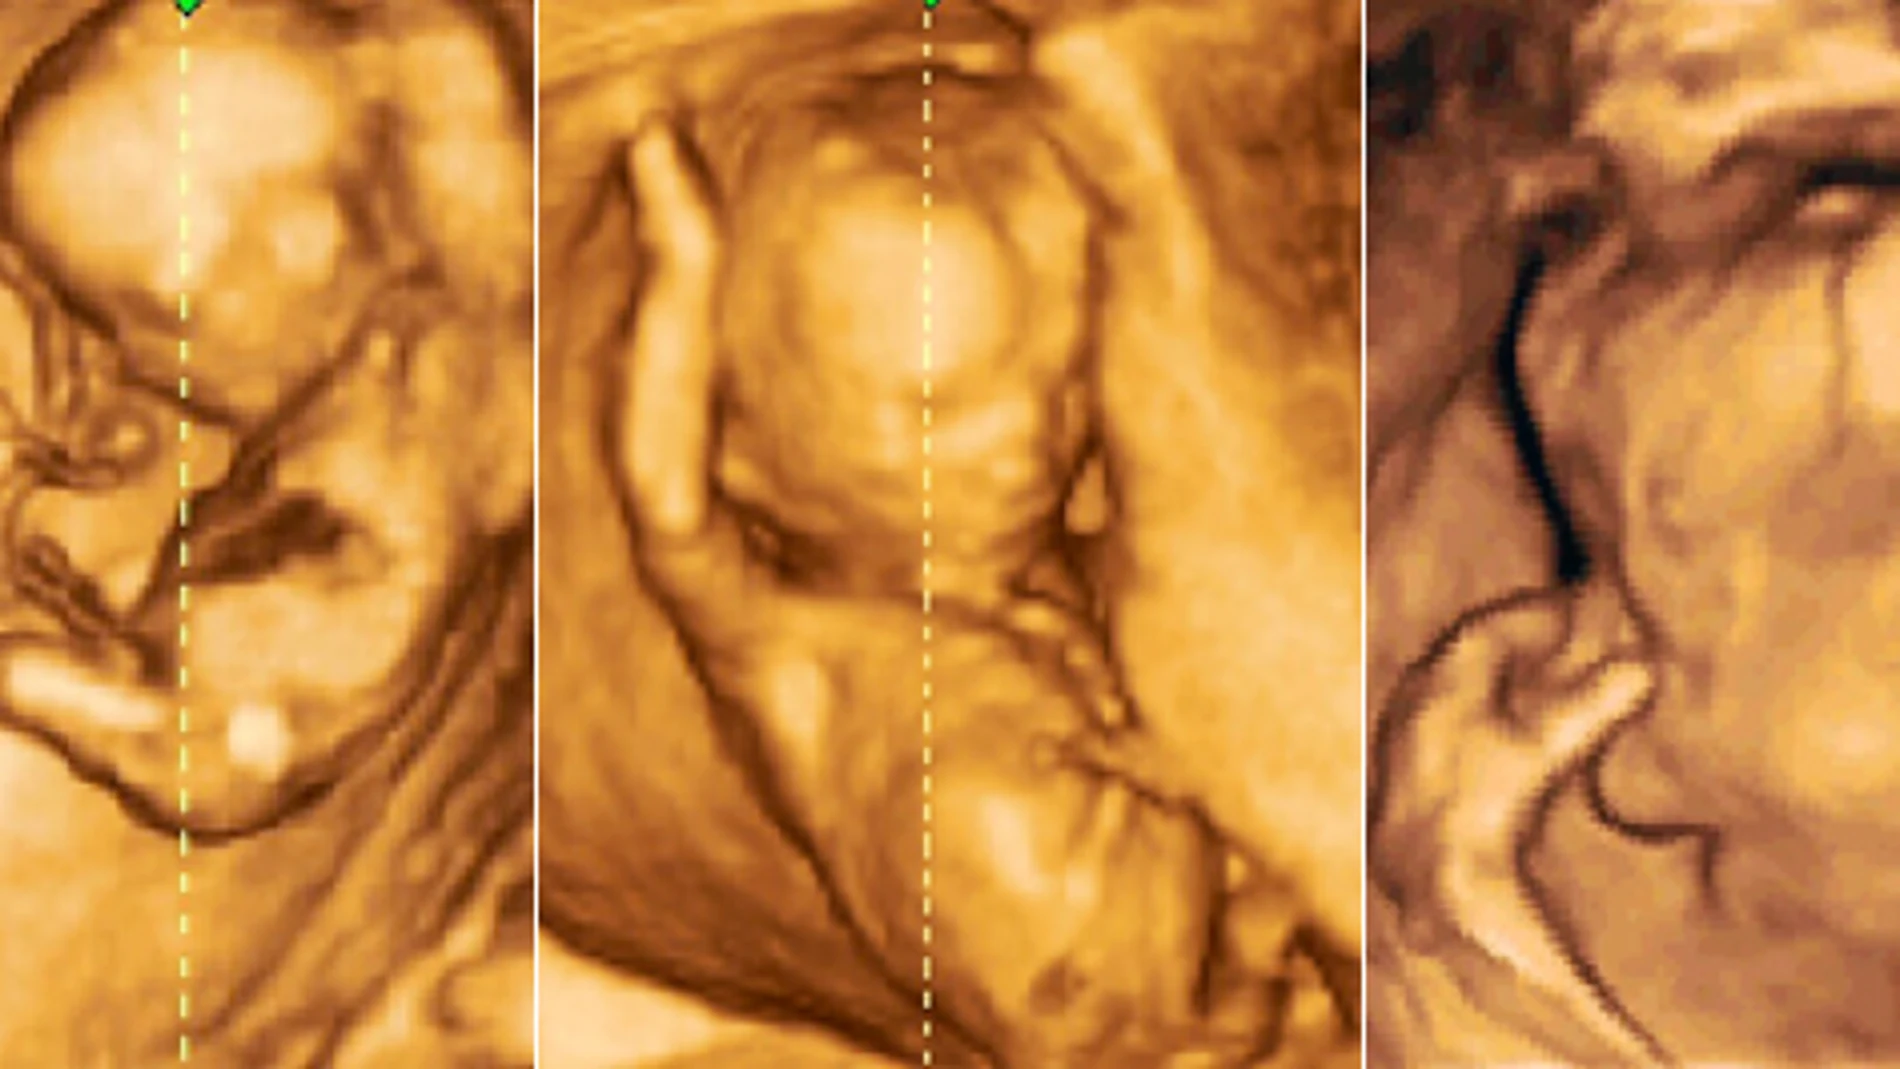

MADRID- El 3,1 por ciento del total de los abortos que se producen en España tiene que ver con malformaciones del feto. Sólo el año pasado supuso que 3.361 niños no nacieran en España por esta causa y, desde que Felipe González lo regulara por ley en el año 1985, más de 45.000. Aunque la cifra puede parecer pequeña, en realidad supone que más del 90% de los fetos diagnosticados como síndrome de Down por los médicos son «eliminados». Y es que, según Esteban Rodríguez, ginecólogo de Derecho a Vivir, el 3,1 por ciento de abortos registrados por el Ministerio de Sanidad, Asuntos Sociales e Igualdad por malformación del feto en realidad coincide con el porcentaje de casos de este tipo que puede registrar la especie humana.

No obstante, el diagnóstico prenatal que se realiza a todas las embarazadas ha provocado un aumento de casos de interrupciones del embarazo por esta causa en los últimos cinco años. Si en el año 2005 se registraron 2.901, en el año 2010, Sanidad llegó a contabilizar casi 500 casos más hasta llegar a los 3.361. La ginecóloga Sonsoles Alonso añade un dato más: «En 2009, hasta un 97 por ciento de las mujeres que abortaron se acogieron a este supuesto. Hablamos de vidas humanas.».